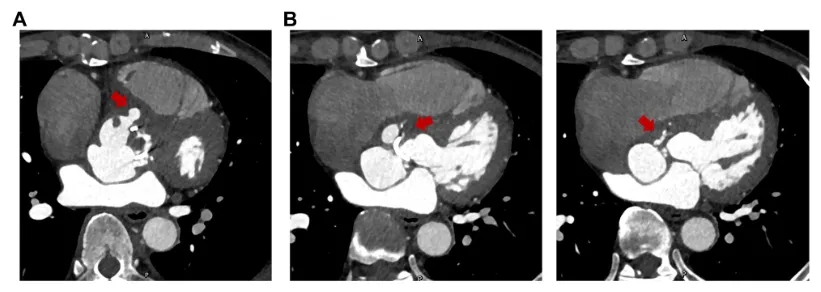

冠脉CT显示右冠窦瓣周脓肿(图2A)伴右冠窦至右心房瘘管形成(图2B)。右冠窦及无冠窦下方有大量脓肿,压迫左心房并侵蚀右纤维三角(图3)。由于赘生物侵袭导致右冠状动脉(RCA)近段慢性闭塞,右冠状动脉中段观察到栓塞碎片(图4)。患者高敏肌钙蛋白(hs-cTn)升高至2090ng/mL符合冠脉栓塞引发的心肌损伤表现,以上共同表明为IE导致的广泛解剖破坏,涉及瓣膜及瓣周结构。

图2